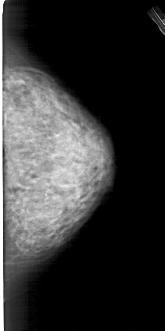

A_1282_1.LEFT_MLO

LEFT_MLO LINES 5491 PIXELS_PER_LINE 2971 BITS_PER_PIXEL 12 RESOLUTION 43.5 OVERLAY